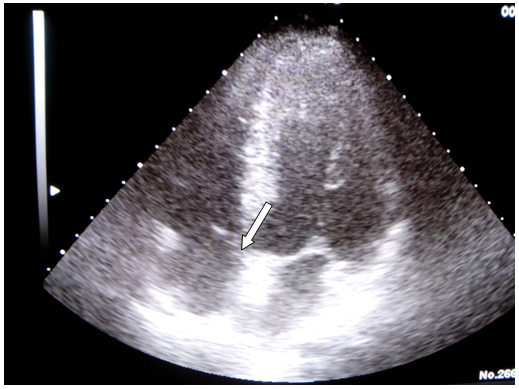

With a diagnosis of brain stroke regarding different vascular regions, the suspected etiology was endocarditis. Blood tests showed increased glomerular sedimentation speed, increased D-dimer (50417) and low platelets (115000). Other complementary exams such as blood serologies, blood and urine cultures were negative. Neurosonological study showed carotid atheromatosis without significant stenosis and a right middle cerebral artery occlusion. In the transthoracic echocardiography a lesion over mitral valvular veil was seen (Figure 2).

Figure 2 Vegetation over mitral vail, showed with transthoracic echocardiography.